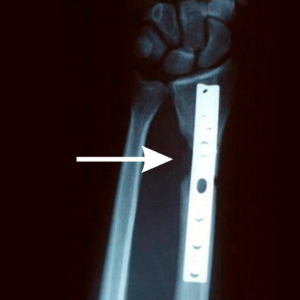

Before X-Rays were taken in 1996 and demonstrate bone loss from saw injury one week post op bone grafting.